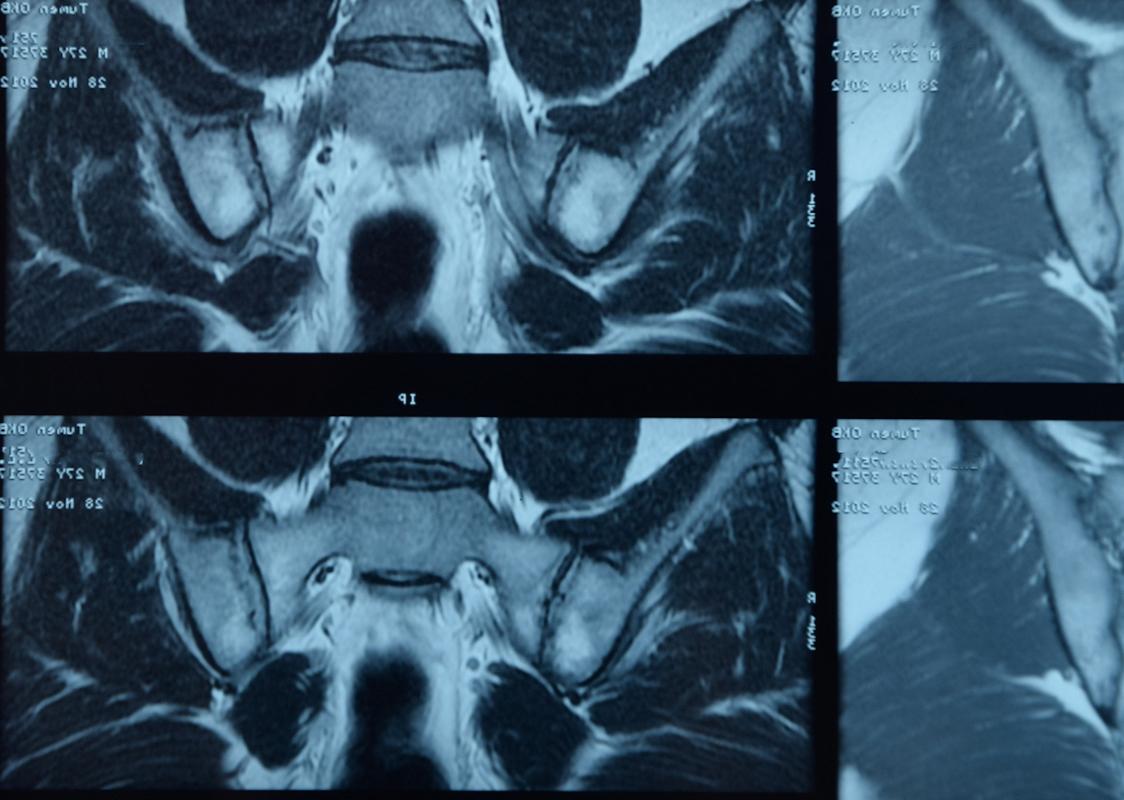

C’est la conclusion d’une étude de cohorte publiée dans Annals of the Rheumatic Diseases ayant suivi au moins 2 ans des lombalgies chroniques adressées à un rhumatologue. Le rendement des évaluations répétées est donc modeste globalement, par contre il peut être utile de répéter l'IRM chez les patients de sexe masculin qui sont HLA-B27+.

Chez les 552 patients souffrant de douleurs lombaires chronique, le diagnostic de spondylarthrite axiale a été posé d’emblée chez 175 (32%) et chez 165 (30%) à 2 ans, alors que le diagnostic de spondylarthrite a été exclu d’emblée chez 40% d’entre eux. Un HLA-B27+ et une imagerie de sacroiliite d’emblée ont permis de mieux prédire quels sont les patients qui seront atteints de spondylarthrite axiale avérée à 2 ans.

Le diagnostic initial est resté relativement stable au cours de ce suivi de 2 ans : le diagnostic initial de spondylarthrite axiale n’a été révisé que chez 5% des patients chez qui on l’avait posé, tandis que 8% des diagnostics douteux ont « progressé » vers un diagnostic avéré de spondylarthrite axiale. Une « bonne réponse » aux anti-inflammatoires non stéroïdiens (réduction de 50% au moins de la douleur lombaire en moins de 48 heures) et une sacroiliite en IRM se sont le plus souvent développées au cours du suivi chez les patients avec un diagnostic incident de spondylarthrite axiale.

Malgré la répétition des examens, l'incertitude diagnostique persiste chez 30% des patients lors du suivi sur 2 ans. Parmi les patients qui ont développé une sacroiliite en IRM, 7/8 étaient HLA-B27+ et 5/8 étaient des hommes. Ainsi, bien que la répétition des examens n’ait apporté qu'une aide « modeste » pour le diagnostic final, il semble que la répétition d’une IRM au fil du temps ne soit contributive que chez les hommes qui sont HLA-B27 positif, bien que ce soit un biomarqueur imparfait de la spondylarthrite.

Le bilan diagnostique comprenait l'évaluation des caractéristiques cliniques de la spondylarthrite, des protéines de l’inflammation, du HLA-B27, des radiographies et de l'IRM (articulations sacro-iliaques et rachis dorso-lombaire), avec des évaluations répétées. À chaque visite (au départ, à 3 mois, à 1 an et à 2 ans), les rhumatologues ont posé un diagnostic de spondylarthrite axiale ou d’absence de spondylarthrite avec leur degré de confiance (LoC ; 0-pas du tout confiant à 10-très confiant). Le critère de jugement principal était le diagnostic de spondylarthrite axiale avec un degré de confiance (LoC≥7 (d-axSpA)) à 2 ans.